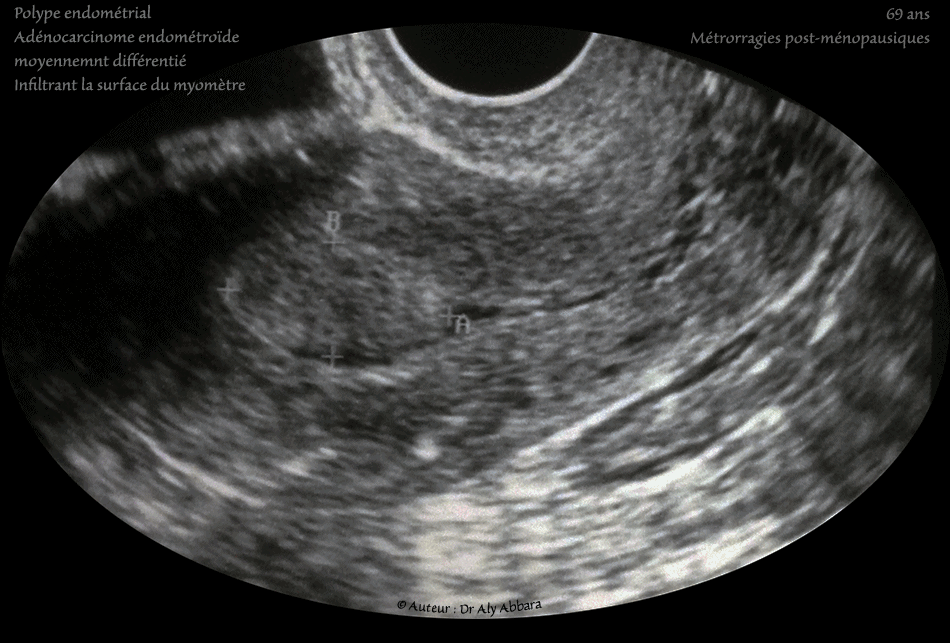

• Images échographiques montrant, sur une coupe sagittale transverse, la présence, au fond utérin, d'une formation polypoïde mesurant 24 x 12 x 23 mm (soit 3,5 cm3).

• La patiente est âgée de 69 ans et se plaignant depuis six mois, de métrorragies répétitives post-ménopausiques (non induites par un traitement hormonal substitutif).

Conclusion : adénocarcinome de type endométroïde moyennement différencié de grade histologique II, infiltrant au moins la partie superficielle du myomètre.